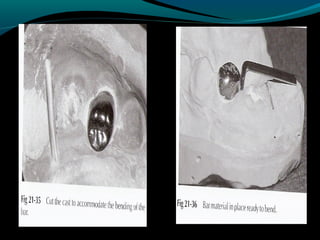

STEPS IN BAND FORMATION-

A) Separation of teeth

By (i) Brass wire

(ii) Elastic threads

B) Band formation

By (i) Direct formation

-Band pinching

-Festooning

-Trimming

-Folded flap

(ii) Preformed bands

(iii) Indirect band technique

C) Welding

D) Soldering